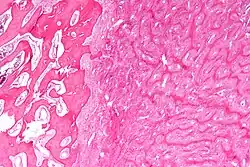

| Micrograph showing fibrous dysplasia with the characteristic thin, irregular bony trabeculae and fibrotic marrow space. H&E stain. | |

Fibrous dysplasia is a mosaic disease resulting from post-zygotic activating mutations of the GNAS locus at 20q13.2-q13.3, which codes for the α subunit of the Gs G protein-coupled receptor.[13] In bone, constitutive Gsα signaling results in impaired differentiation and proliferation of bone marrow stromal cells.[14] Proliferation of these cells causes replacement of normal bone and marrow with fibrous tissue. The bony trabeculae are abnormally thin and irregular (bony spicules on biopsy).